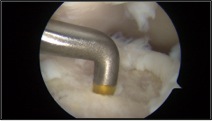

Nei casi più importanti, dove le lesioni cartilaginee sono più gravi e localizzate in zone di carico dell’astragalo, una valida soluzione è rappresentata dall’utilizzo di tecniche chirurgiche avanzate di riparazione cartilaginea che utilizzano supporti tridimensionali in grado di veicolare le cellule cartilaginee e colmare così il difetto che si è creato. Queste tecniche possono essere eseguite anche in artroscopia con maggior rispetto dell’articolazione e tempi di recupero post-operatorio di circa 3-4 mesi.